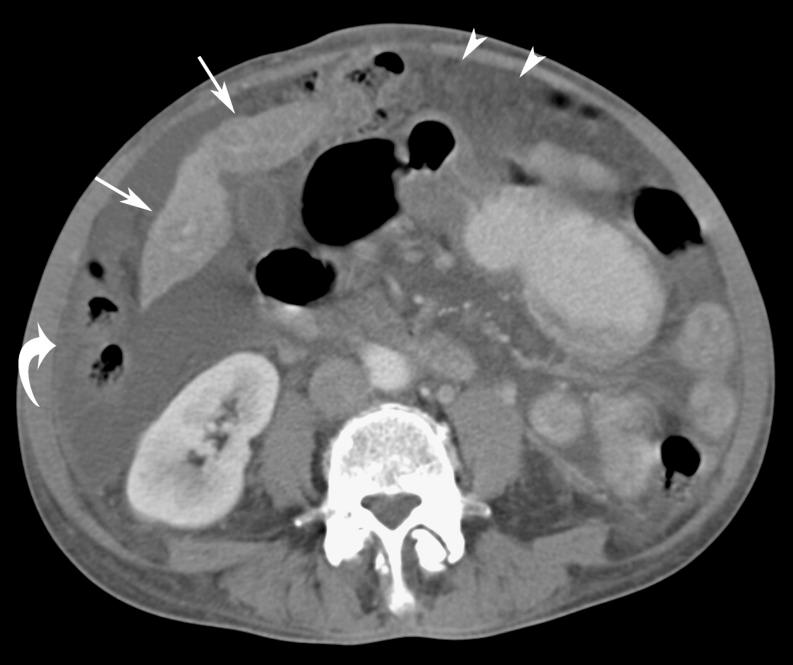

Omental cakes typically are associated with ovarian carcinoma, as this is the most common malignant aetiology. Nonetheless, numerous other neoplasms, as well as infectious and benign processes, can produce omental cakes. METHODS: A broader knowledge of the various causes of omental cakes is valuable diagnostically and to direct appropriate clinical management. RESULTS: We present a spectrum of both common and unusual aetiologies that demonstrate the variable computed tomographic appearances of omental cakes. CONCLUSION: The anatomy and embryology are discussed, as well as the importance of biopsy when the aetiology of omental cakes is uncertain.